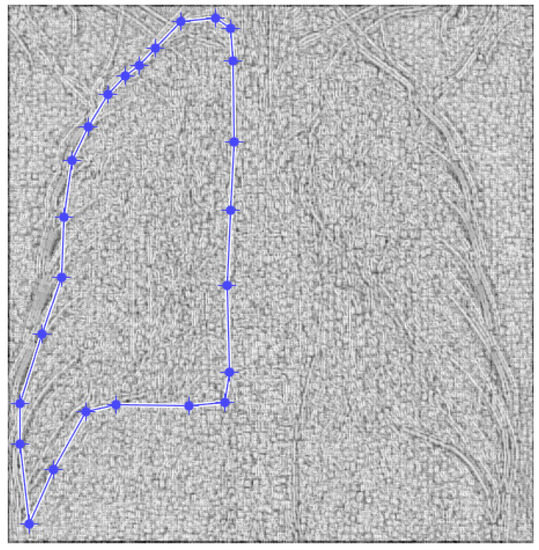

Figure 4. Defining the mask for the left lung of the first patient.

Figure 4 and Figure 5 present the defined masks for the left lung and right lung, framed in blue borders.

Table 1 shows the known fractal indicators, such as the fractal dimension of the CT image of the left lung, d1L = 1.8781 ± 0.3251, and the lacunarity, Λ = 0.0300; and the fractal dimension of the right lung, d1R = 1.8817 ± 0.3267, and the lacunarity, Λ = 0.0301.